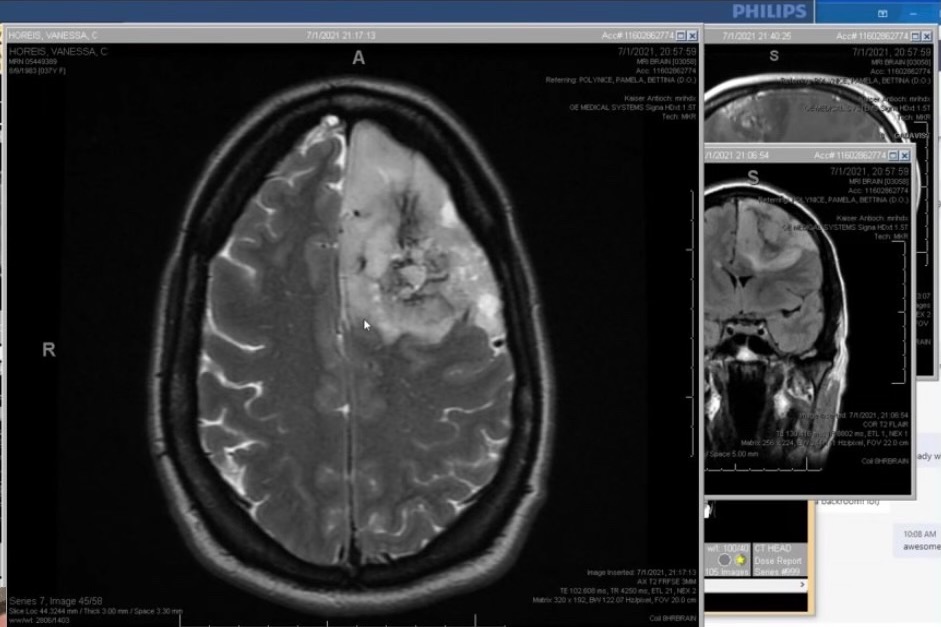

Vanessa has been diagnosed with a brain tumor that needs to be removed immediately. With the loving support of her husband, Erich, they have jumped into developing a plan to rid her body of this very large tumor ASAP. Anyone who knows Vanessa - personally or professionally- will tell you Vanessa has a huge heart and a lot to live for. The tumor has to GO!

Recovery from this surgery is not quick – THEY ARE REMOVING A HUGE SECTION OF MY BRAIN, so not everything goes right back to normal. It will be a many months long process and there is a chance it may involve more or less therapies (both neuropsych and speech and language, all of which UCSF has), depending on multiple factors.